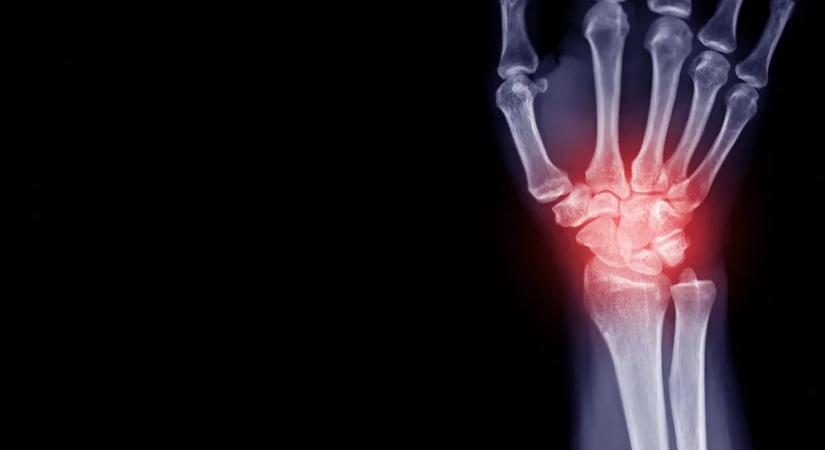

Rémisztő dolgot találtak az emberi csontban; mindannyiunkban ott lehet

A tudósok eddig főként a vérben, a tüdőben és a szívben azonosítottak mikroszkopikus műanyag-részecskéket.